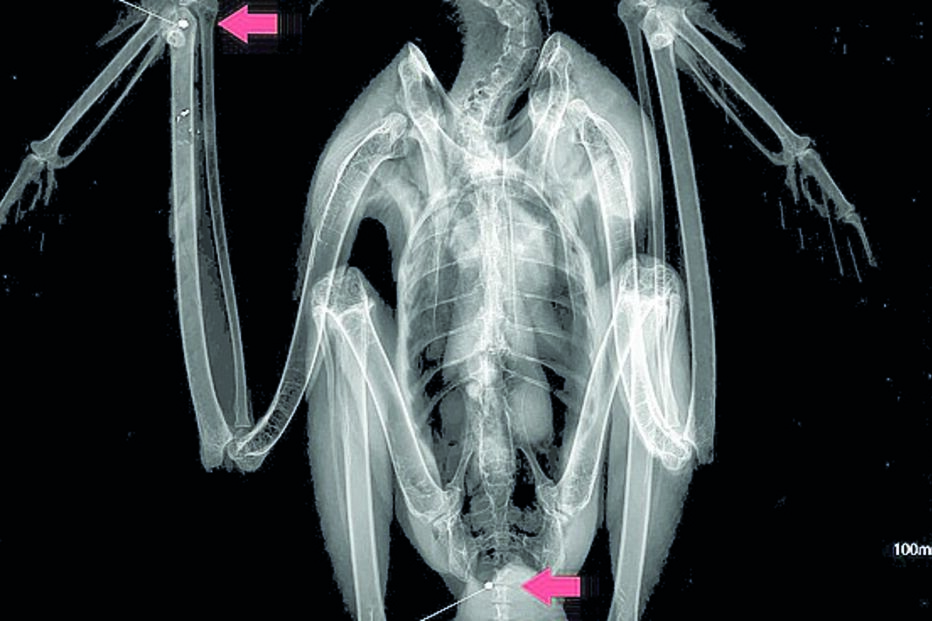

Ave foi atingida por vários projéteis. Foi encontrada por um popular.

No exame radiológico "foram encontrados dois projéteis de caçadeira no pulso direito e na cauda, mas também uma fissura no cúbito direito, que apresentava ainda restos de munição", esclareceu a mesma fonte.